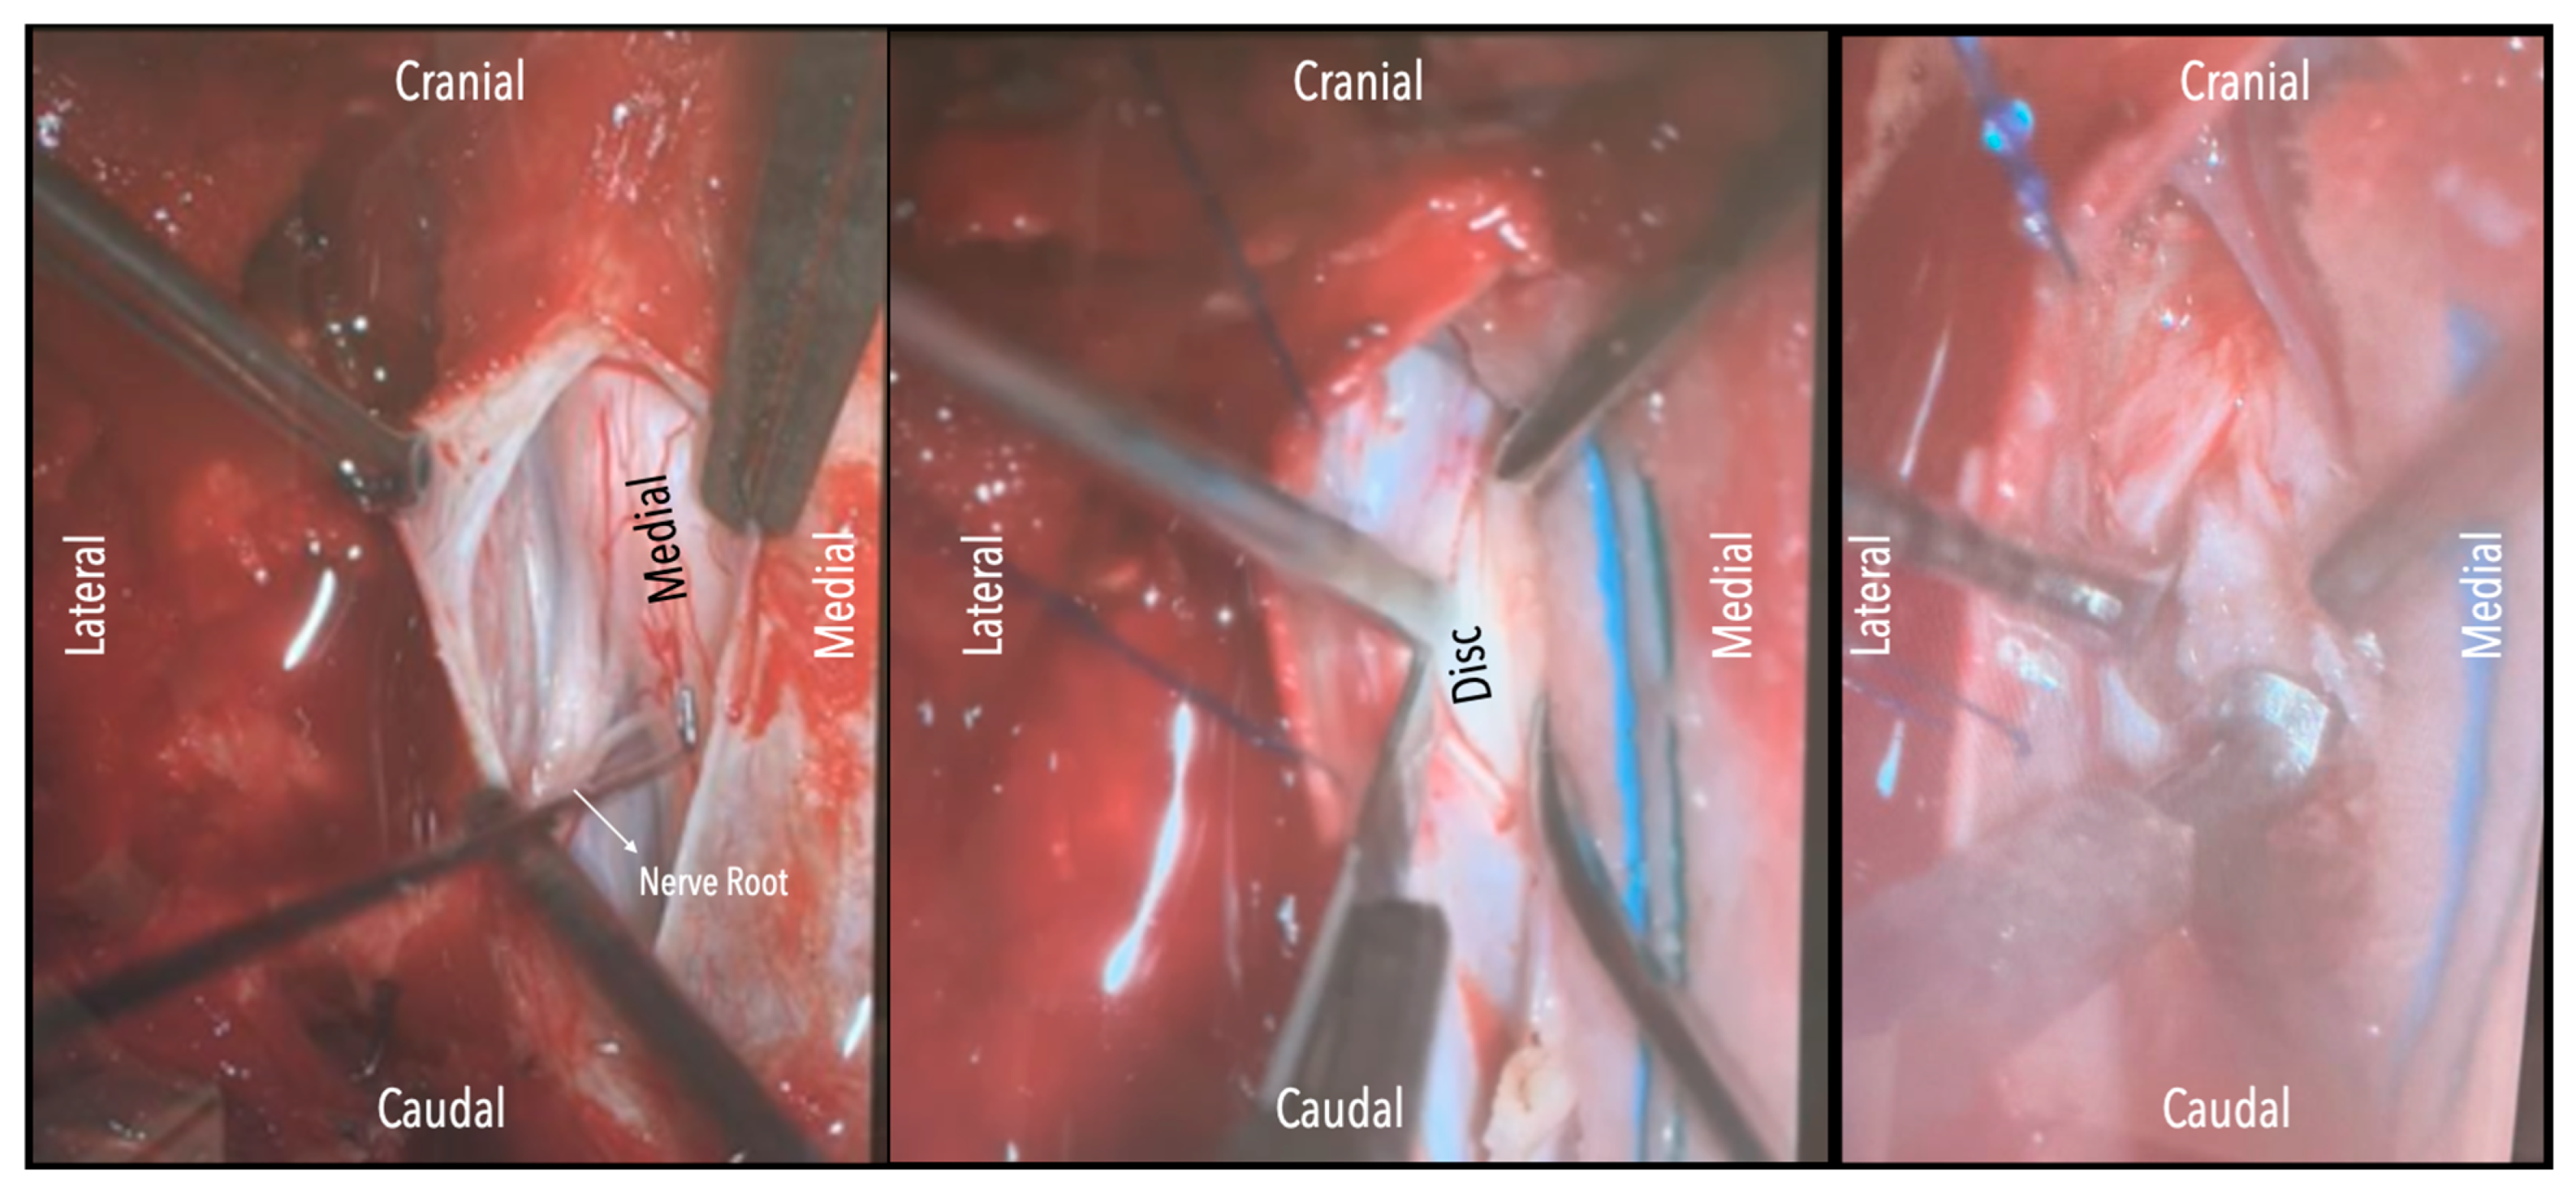

A wide en bloc laminectomy was performed at the disc level and one level above and below using a Misonix bone scalpel. This was followed by ipsilateral superior and inferior facetectomies and complete pediculectomy to establish an oblique and spacious working corridor toward the ventral spinal canal (Figure 1). Under the operating microscope, the dura was opened in the midline with a no. 15 blade, and the arachnoid was incised sharply. CSF was allowed to drain passively for 10–15 min to reduce intradural pressure and promote relaxation of the spinal cord. The table was then tilted approximately 6–10 degrees to the contralateral side to allow for gravity-assisted displacement of the cord away from the operative field (Figure 2a,b and Figure 3).

In three of the seven cases, the exiting nerve root at the level of the herniation was ligated due to poor visualization and transected extradurally to improve access. In the remaining four patients, the nerve root was either preserved or dissected intradurally using isocool bipolar diathermy and microsurgical scissors. With gentle medial retraction of the cord under gravity and protection using a micro-patty, the calcified disc was exposed. The ventral dura, when intact, was incised sharply and dissected from the disc surface where possible (Figure 2a,b and Figure 3). Disc removal was performed using a hockey-stick-shaped Misonix bone scalpel with constant irrigation, guided by intraoperative neuronavigation. The disc material was resected to a depth of 1–2 mm beyond the posterior vertebral wall to ensure adequate decompression. A second O-Arm spin was routinely performed following discectomy to confirm satisfactory decompression, especially given the limitations of the postoperative MRI due to the metal artefact (Figure 4, Figure 5 and Figure 6).

Figure 2. (a). Surgical field under microscope magnification. A: Opening of dura with no. 15 blade. B: Release of CSF. Following this, the table was tilted contralateral to the disc side to allow the cord (see annotation in image on the left) to slowly drift away. The dentate ligament, appearing as a thickening of the arachnoid, can be identified and dissected with microscissors. C: The nerve root is evident. If required, it could be sacrificed intramurally (see dashed line and annotation in image on the left side) with microscissors after being coagulated with bipolar diathermy. (b). Intraoperative microscope view of the same case. Right-sided disc. A: The calcified disc is evident after gentle gravity-retraction of the cord. B: A hockey stick bone scalpel (MISONIX). C: Watertight closure of dorsal dura.

Figure 3. Intraoperative microscope view. Left-sided disc. Left: After opening the dura mater, the nerve root and cord are evident. Middle: Following drainage of CSF, dissection of the dentate ligament and gravity retraction, a micro-pattie is applied on the lateral aspect of the cord and a penfield microdissector is used to gently retract the cord, and the disc becomes evident. Right: Discectomy is carried out with a hockey stick bone scalpel.